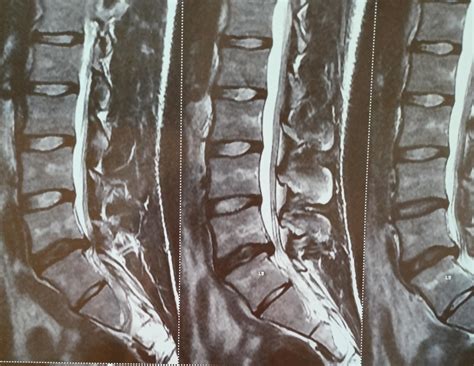

Diagnosing Grade 1 Retrolisthesis

Diagnosing Grade 1 Retrolisthesis typically involves a combination of physical examinations and imaging tests. The diagnostic process may include:

• Imaging Tests: X-rays, CT scans, and MRI scans to visualize the spine and identify any misalignments.

Imaging tests are particularly crucial for diagnosing Grade 1 Retrolisthesis, as they provide a clear view of the vertebrae and any slippage. MRI scans are often preferred for their detailed images of soft tissues, which can help identify nerve compression and other issues.